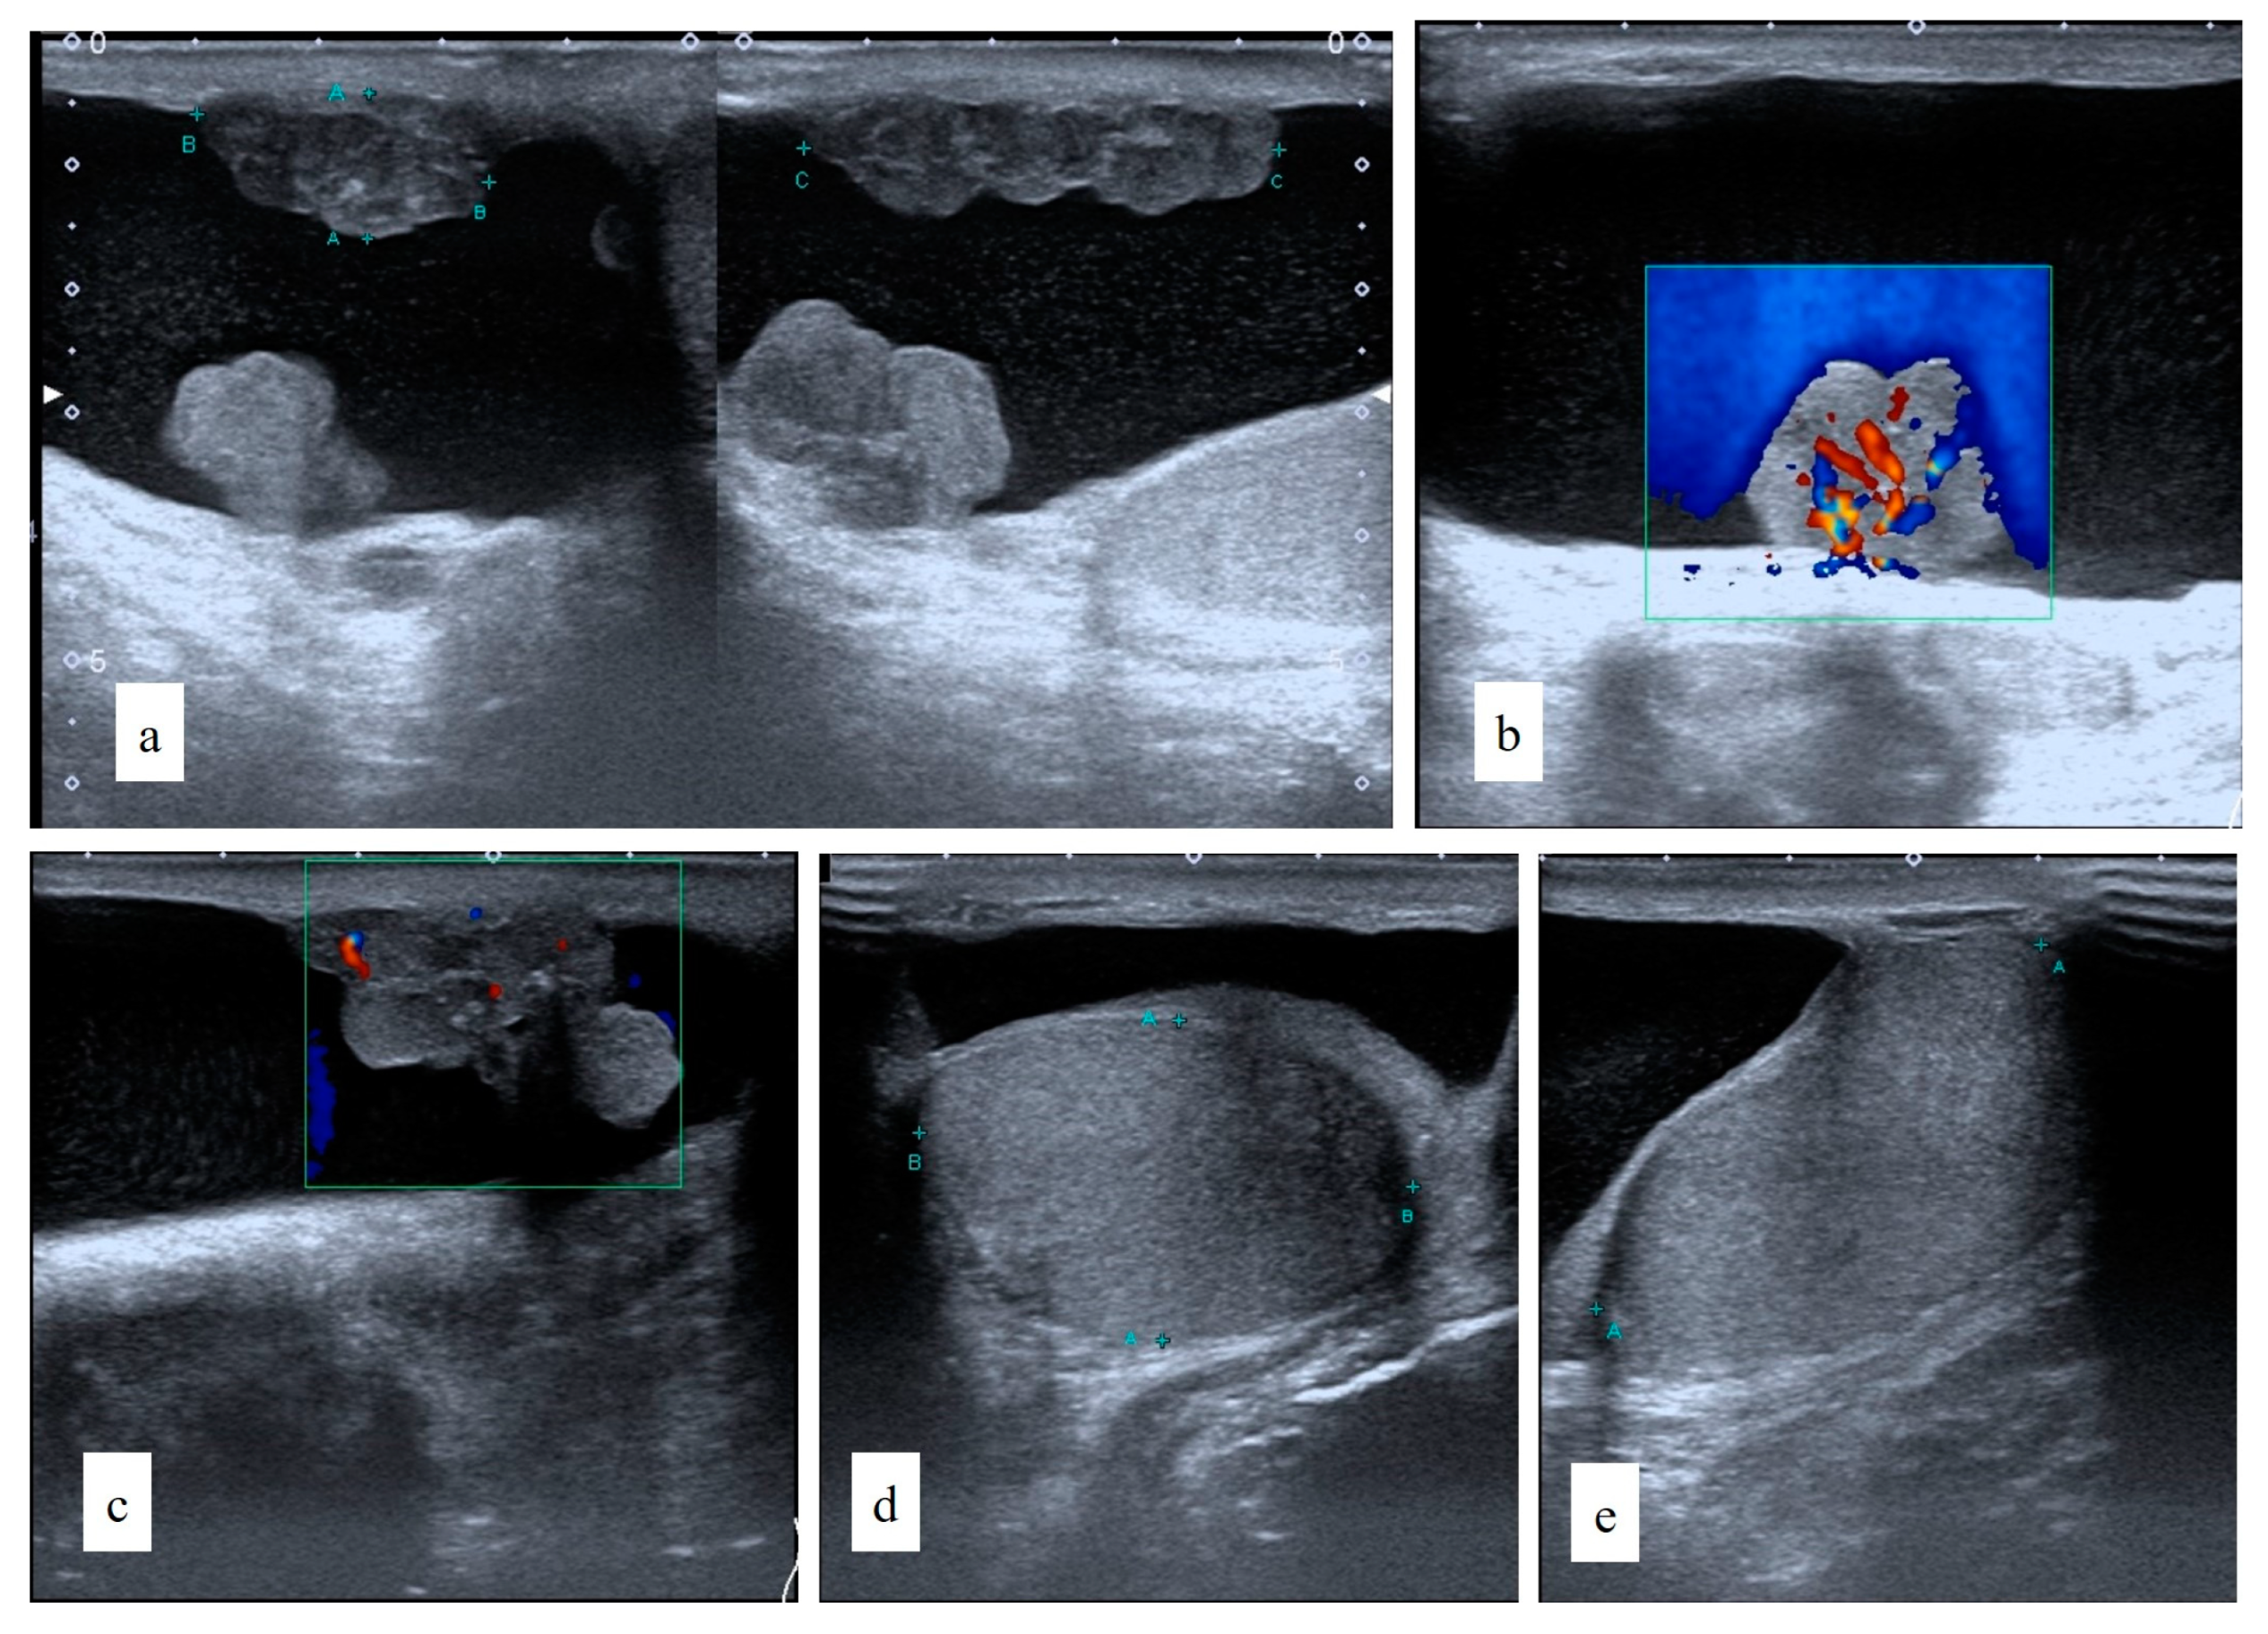

2. Case Report